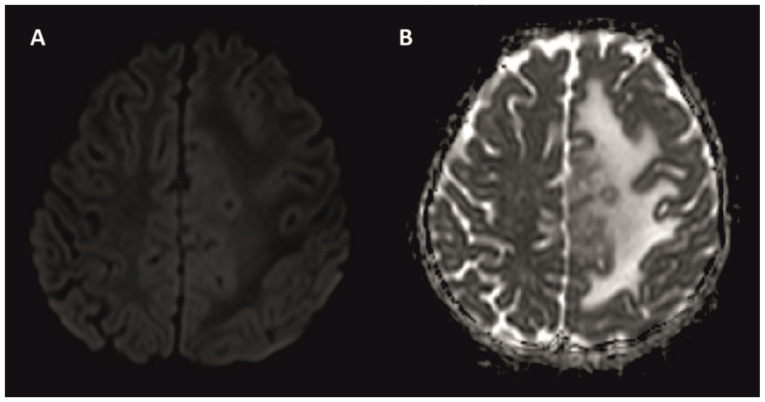

颅内结核瘤是中枢神经系统结核(TB)最严重的并发症之一,发病率相对较低。在颅内结核瘤病例中,患者在接受抗结核治疗时可能出现药物毒性和/或免疫重建炎症综合征(IRIS)。目前的研究报告了一名7岁的颅内结核瘤女性患者在治疗过程中出现药物性肝毒性和IRIS。在患者随访期间,出现抗结核药物性肝炎,导致两次停药。在治疗的第七个月,颅脑MRI显示结核瘤病变的进展。考虑到IRIS或治疗失败的可能性,重新开始使用类固醇和非肝毒性抗结核药物治疗。通过类固醇和抗结核治疗,病变几乎完全消退,神经功能缺损也得到了缓解。由于抗结核药物可能产生的副作用,特别是IRIS,应密切随访接受治疗的患者,IRIS是在免疫系统恢复过程中作为免疫重组反应而发展起来的。

Intracranial tuberculoma represents one of the most severe complications of central nervous system tuberculosis (TB), with an incidence that is relatively low. In cases of intracranial tuberculoma, patients may develop drug toxicity and/or immune reconstitution inflammatory syndrome (IRIS) while receiving anti-TB treatment. The current study presented the case of a seven-year-old female patient with intracranial tuberculoma who developed drug-induced hepatotoxicity and IRIS during the course of treatment. During the follow-up of the patient, anti-TB drug-induced hepatitis developed, which led to the discontinuation of the drug twice. In the seventh month of treatment, cranial MRI showed the progression of tuberculoma lesions. The possibility of IRIS or treatment failure was considered and the treatment was restarted with steroids and non-hepatotoxic anti-TB drugs. With steroid and anti-TB treatment, the lesions regressed almost completely and the neurological deficit regressed. Patients receiving treatment should be followed up closely due to the possible side effects of anti-TB drugs, especially IRIS, which develops as an immune restructuring response during the recovery of the immune system.